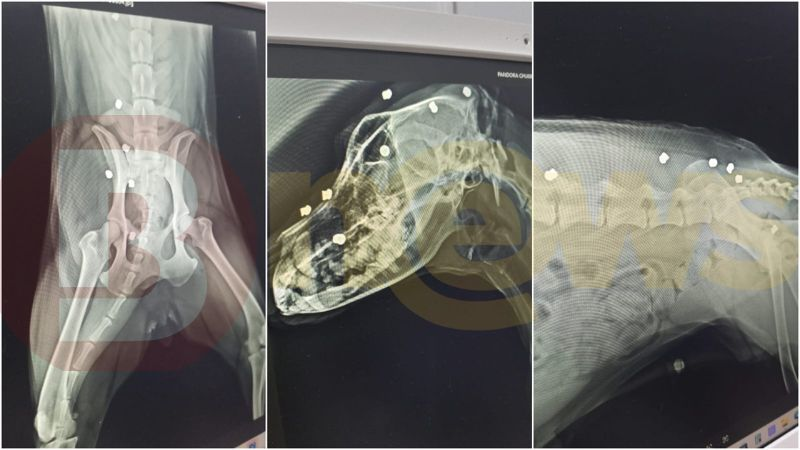

Segundo relatos de vizinhos feitos à reportagem, o morador identificado apenas como Marcones teria atirado 17 vezes com uma espingarda de ar comprimido contra o cachorro de um vizinho após uma discussão. O animal havia fugido da área onde vive e entrou no terreno do suspeito. Outro relato afirma que o agressor atirou no animal mesmo sem qualquer ameaça.